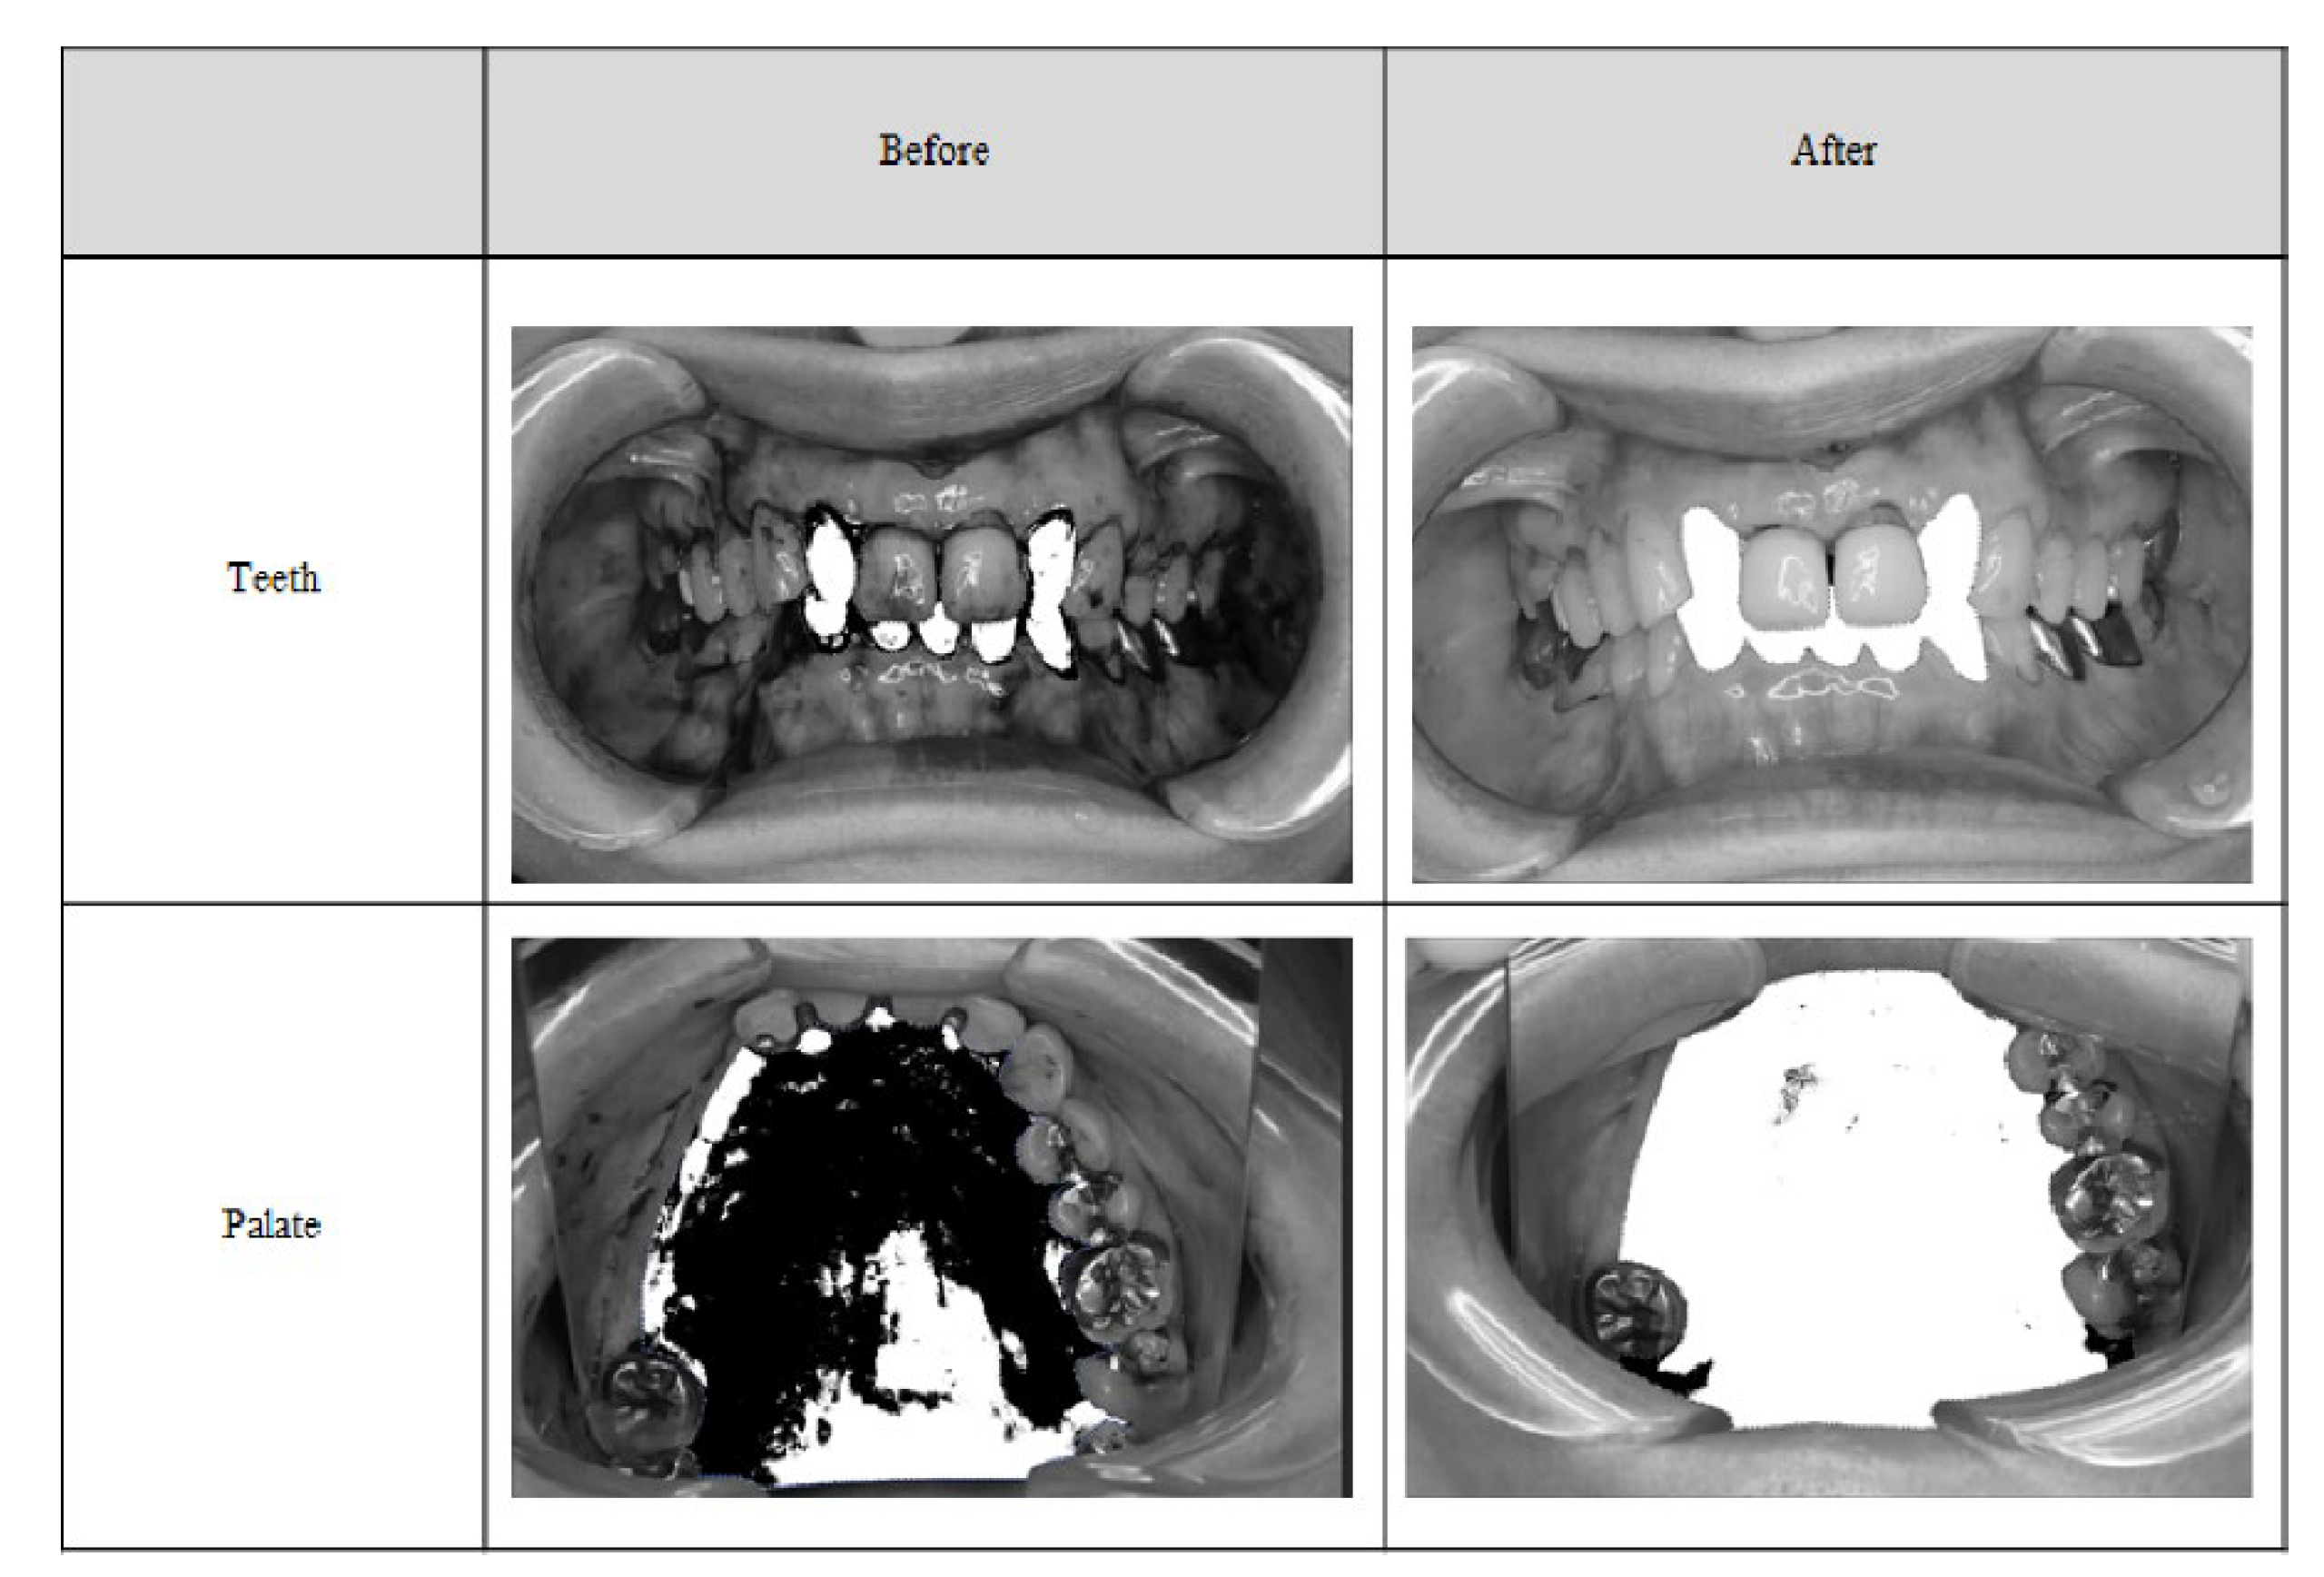

Figure 4.

Teeth and palate photographs before and after the binarization.

2.4. Plaque Removal Rate by Binarization

The removal rate by binarization was 80.47% for the tooth surface and 96.3% for the palate (Table 4).